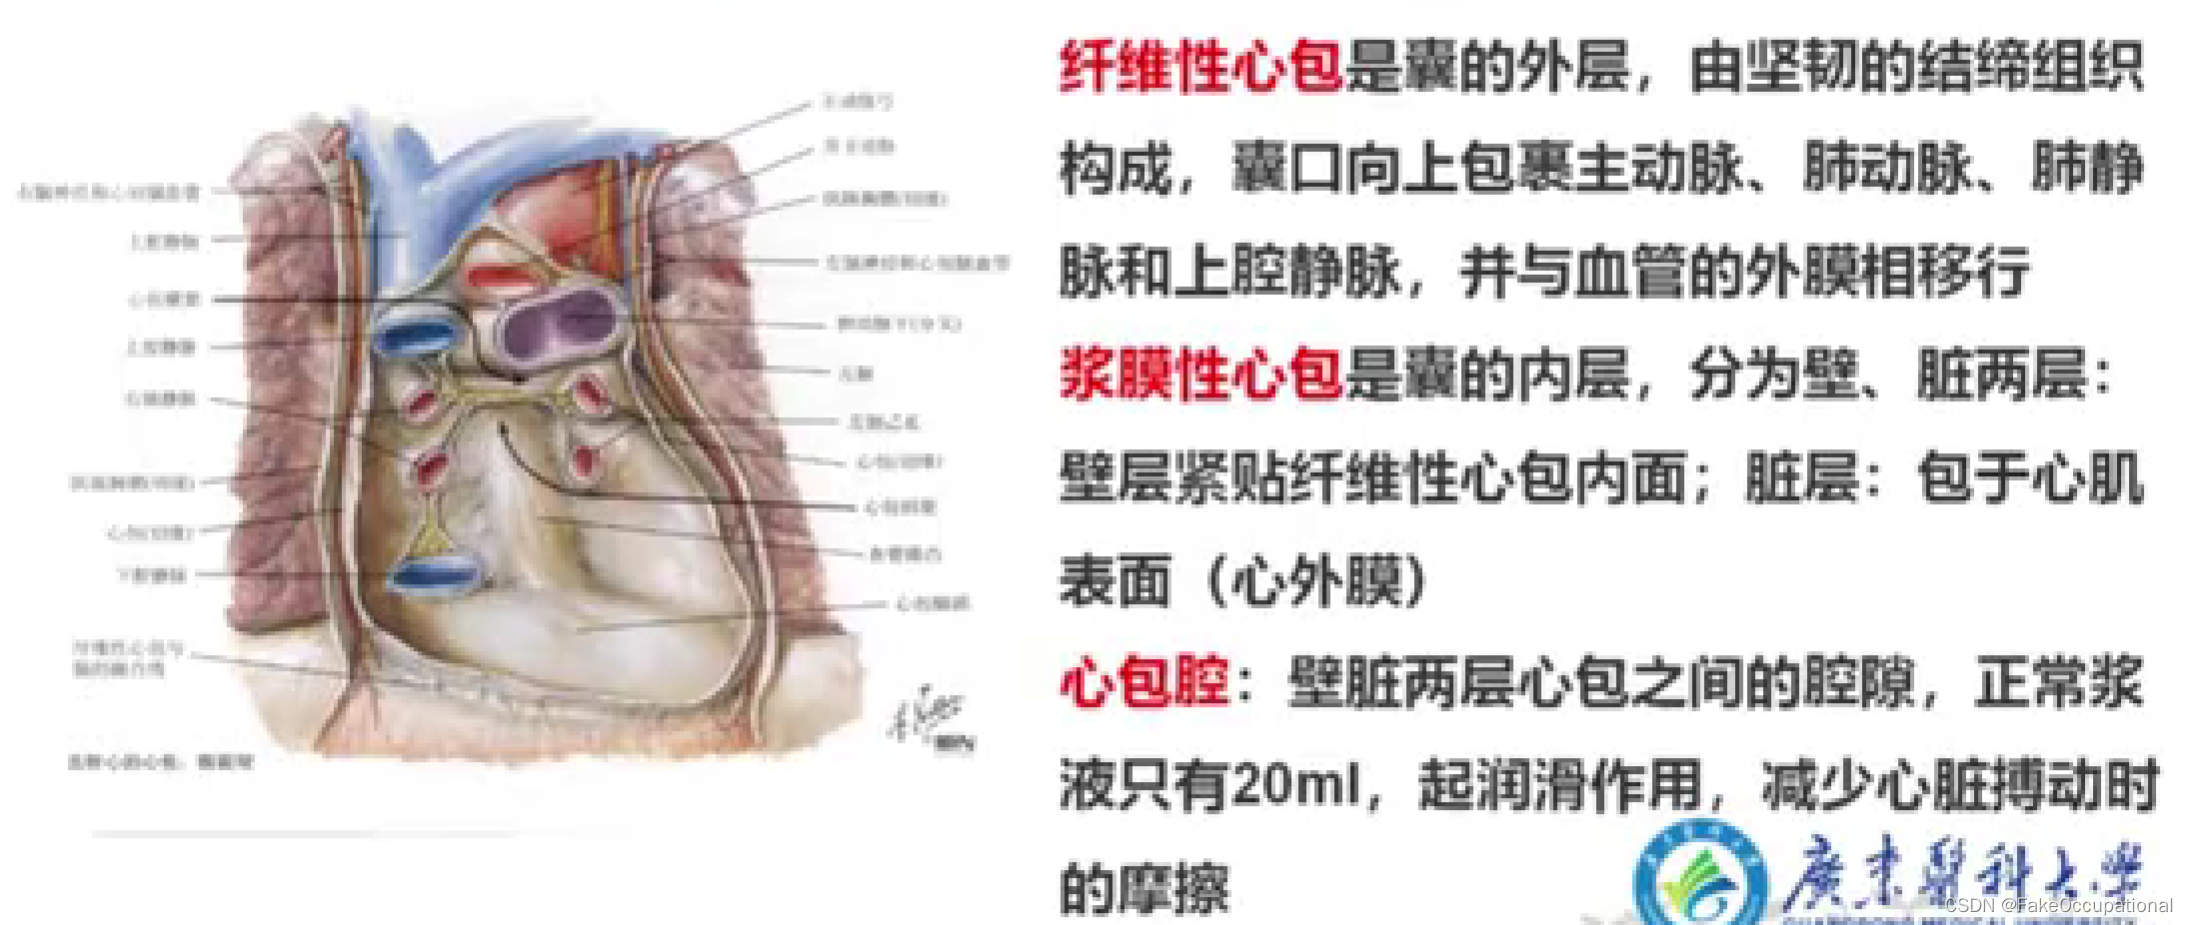

心脏解剖及生理概要

- 心包积液可出现于整个心包,也可局限于心包的局部,但心底部上方和心房后方很少发生液体积聚。心包积液时,心包腔可向内、外侧及心尖方向扩大。心包积液是心包炎最重要的表现之一,但心包炎并非必然出现心包积液。

心包积液超声定量

- 微量 (<50ml) : 左室后壁D2-3mm,右室前壁无液暗区;少量 (50-200ml) :左室后壁D10mm以内,右室前壁无或可疑液暗区;

- 中量 (200-500ml) : 左室后壁D10-20mm,右室前壁D5-10mm;

- 大量 (>500ml) :左室后壁D>20mm,右室前壁D>15mm,可出现心脏摆动征